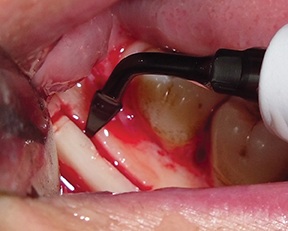

Using an ultrasonic device with dedicated T-Black inserts (ES007T and ES009NT), a cortico-cancellous bone block was outlined and osteotomized (Figs. 7–8).

Fig. 7: Osteotomy performed with an ultrasonic tip (ES009NT)

Fig. 8: Osteotomy performed with an ultrasonic tip (ES007T)